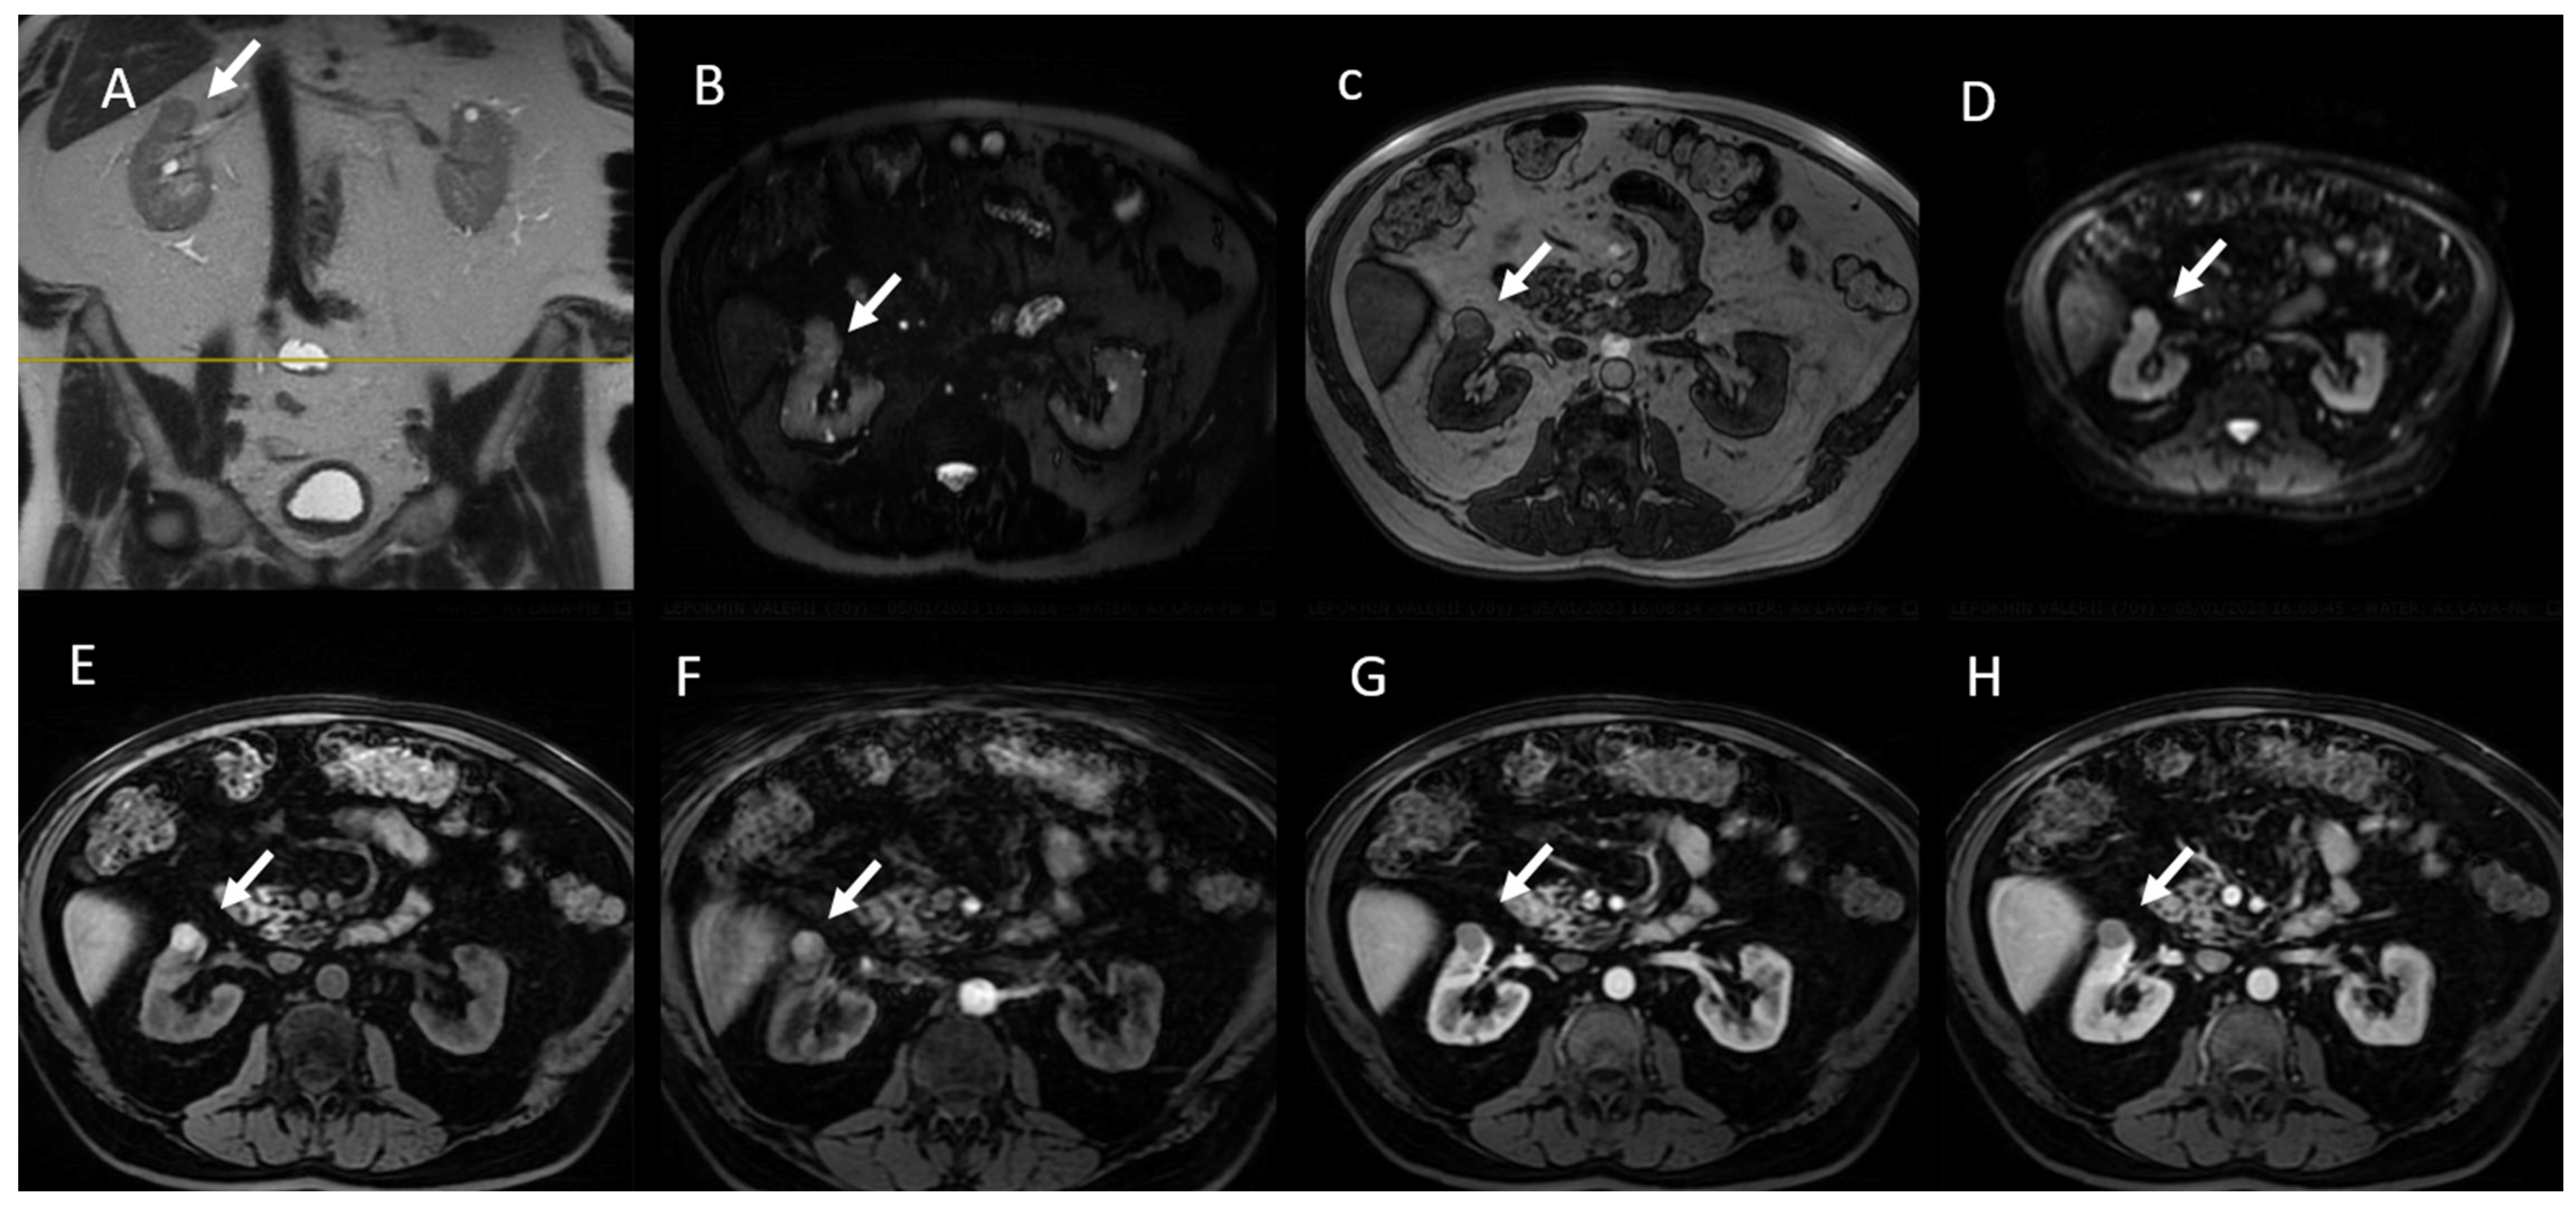

6. MRI Assessment

6.1. T2W Imaging

6.2. CS (IP D OP) Imaging

6.3. Diffusion-Weighted Imaging

6.4. Gadolinium-Enhanced Sequences